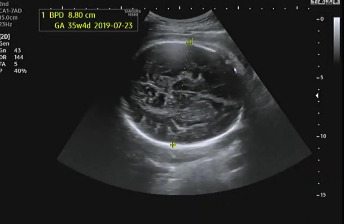

임신 37주가 되어 병원에 내원했다. 초음파를 보는데 아기는 건강하게 잘 있다고 열심히 태동을 하며 인사를 건네 왔다. 머리둘레(BPD), 허벅지 둘레(FL), 복부둘레(AC)를 측정하고 태아가 어느 정도로 성장하였는지 확인했다. 다행히 아기의 머리둘레가 주수보다 작게 나와서 자연 분만하기 좋을 것이라고 이야기를 했다.